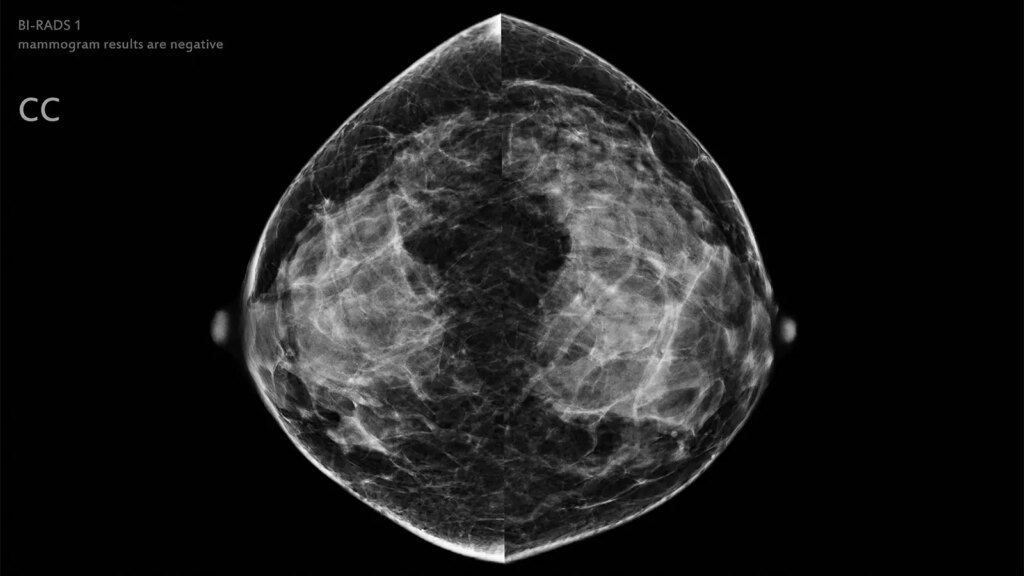

- A partially autonomous AI approach to breast cancer screening could safely eliminate the need for radiologist review of low-risk mammograms, a study suggested.

Artificial intelligence (AI) could potentially be used to safely exclude low-risk mammograms from radiologist review, according to results from a prospective noninferiority trial.